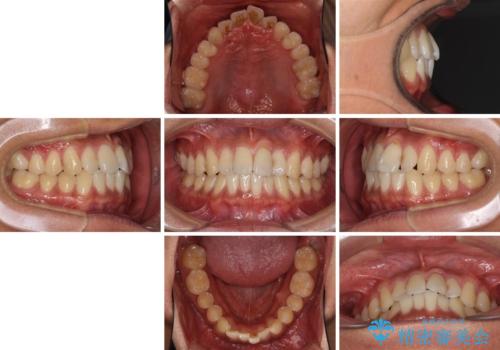

気になる前歯のデコボコをインビザラインで解消

- 前歯のデコボコを気にして来院された患者様です。

主に下顎歯列全体の後方移動とIPR(歯と歯の間を削る)によってデコボコが解消するように設計し、インビザラインにより治療を行うこととしました。

インビザライン矯正特有の、治療後半で前歯のみが強く接触する症状が発現し、咬み合わせ改善に期間を要することとなりました。